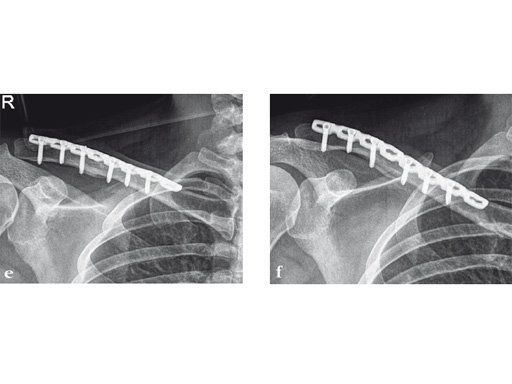

Case 1: a 30-year-old woman sustained a midshaft clavicle fracture. it healed with 2.1 cm shortening over 4 years after nonoperative treatment.

Case provided by Norbert Sdkamp and Martin Jaeger, Freiburg, Germany